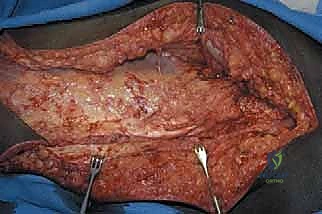

TECH FIG 1 • Initial exposure, showing the planned incision and the development of myocutaneous flaps.

"Now we're through the subcutaneous tissue. We'll incise the fascia lata along its entire length, exposing the underlying muscle groups. With the fascia lata exposed, we can now clearly visualize the hip girdle muscles. We'll internally rotate the hip slightly to bring these muscles into better view. Take a moment to appreciate the anatomy here, fellows. The tensor fasciae latae, the gluteal muscles, the sartorius, the rectus femoris – all are becoming apparent."

TECH FIG 2 • The entire femur has been exposed, disconnected from the hip capsule, and removed. Note the tagged muscle ends and hip capsule for later reconstruction.